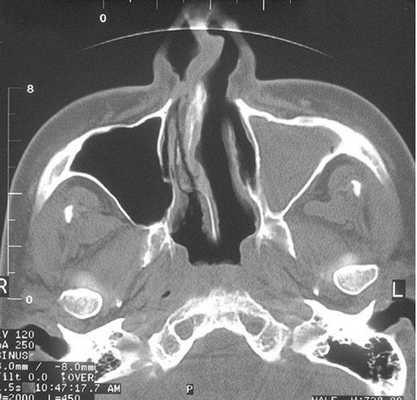

Тотальное заполнение жидкостью (кровью?) левой верхнечелюстной пазухи, повреждение носовой перегородки на компьютерной томограмме

Что показывает КТ пазух носа